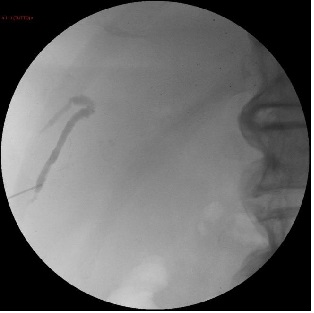

TECHNIQUE : BILIARY CATHETERIZATION